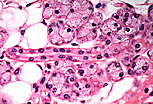

管腔狭窄的排泄管(唾液腺闰管)由单层立方上皮细胞衬贴而成。